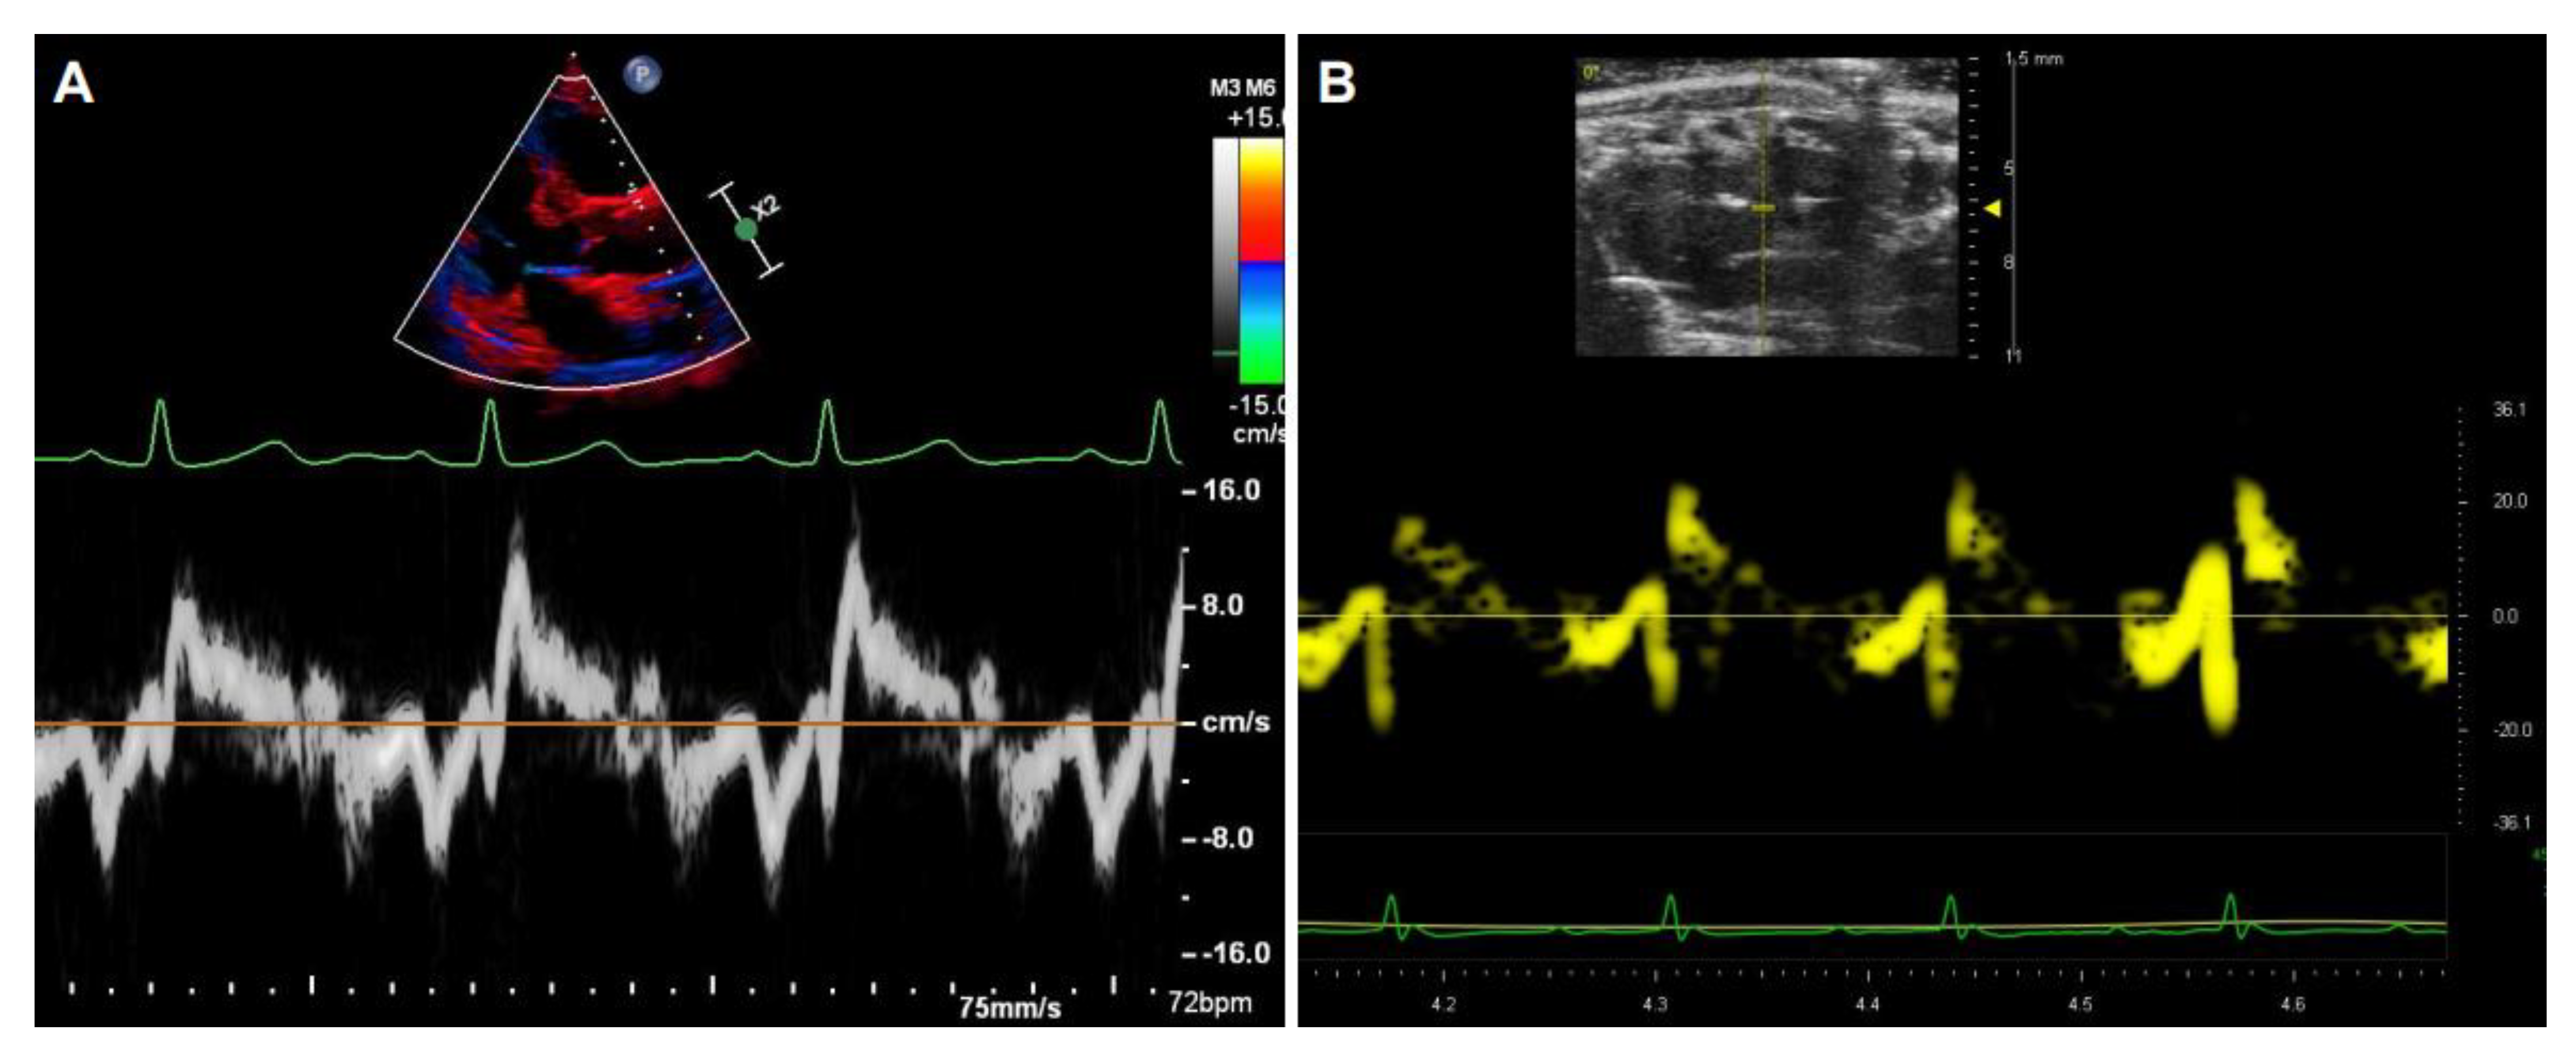

In addition to detecting the blood flow within the aorta, Doppler signals can also be collected from tissue and recorded by TDI, either as spectral or color displays, which can be used to measure tissue stiffness with the velocities and strain rate of the tissue motion. The image acquisition of the aorta by TDI is similar between humans (Figure 8A) and rodents (Figure 8B).

Figure 8. Representative images of the aorta and the waveforms by tissue Doppler imaging. The segmental velocity information of the anterior wall of the aorta in human (A) and mice (B).